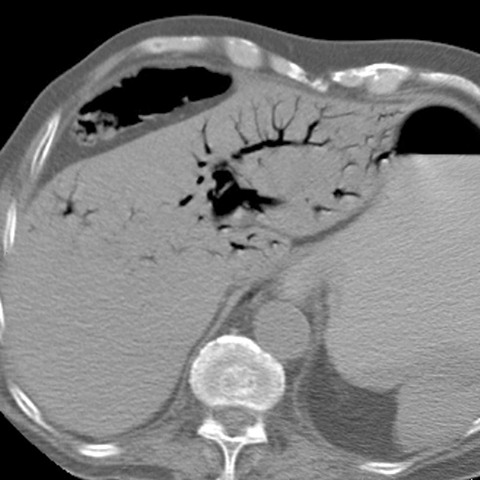

Small Bowel Infarction, axial CT [1 of 2]